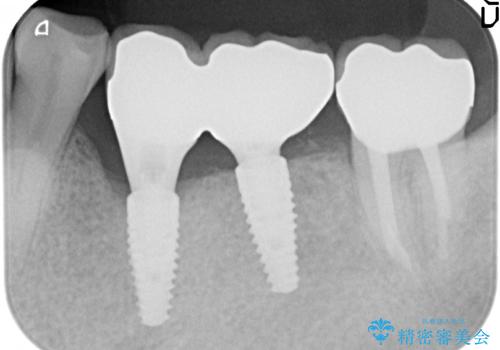

- 右上1の前歯の見た目が気になるので被せ物をやり替えたいといらっしゃった方の症例です。

再根管治療終了後、オールセラミッククラウン(スペシャル)によって隣在歯に合わせた補綴を行いました。